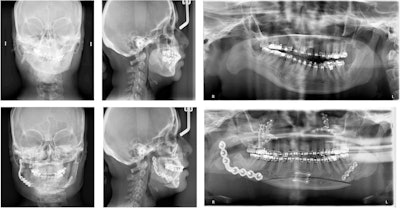

In July 2017, the woman visited the oral and maxillofacial surgery clinic due to her poor bite and facial asymmetry. A physical exam revealed that she had a severe 10-mm occlusal cant, only contacting on her right premolars and molars, with a left-sided open bite. This caused a 2-mm incisal display in repose and a negative 2-mm gum display when she smiled. When smiling, the cant caused a 3-mm gingival display on her left and a negative 4-mm gingival display on the right. Also, her chin deviated dramatically to the right of the midline of her face, the authors wrote.

At the end of the appointment, she was referred to orthodontics for presurgery leveling, aligning, overcrowding correction, and dental decompensation. Six months prior to surgery, the woman's first premolars and remaining third molars were extracted.

In December 2020, she was placed under general anesthesia and underwent the following procedures:

- LeFort I maxillary osteotomy

- Right mandibular inverted L ramus osteotomy

- Left mandibular sagittal split ramus osteotomy

- Genioplasty

- Reconstruction of the right mandibular ramus

- Right zygomaticomaxillary buttress with an anterior iliac crest bone graft

Her procedures went well. For four weeks, maxillomandibular fixation was maintained. Guiding elastics were then used until the seventh week. At that time, the woman's face was largely symmetrical, and she was healing without complications.

After the procedures, the woman was seen every week for eight weeks and then at three months. At the three-month appointment, clinicians found that she had developed a 2-mm anterior open bite with equal contacts on her second molars. Using orthodontic intrusion, the open bite was closed, the authors wrote.